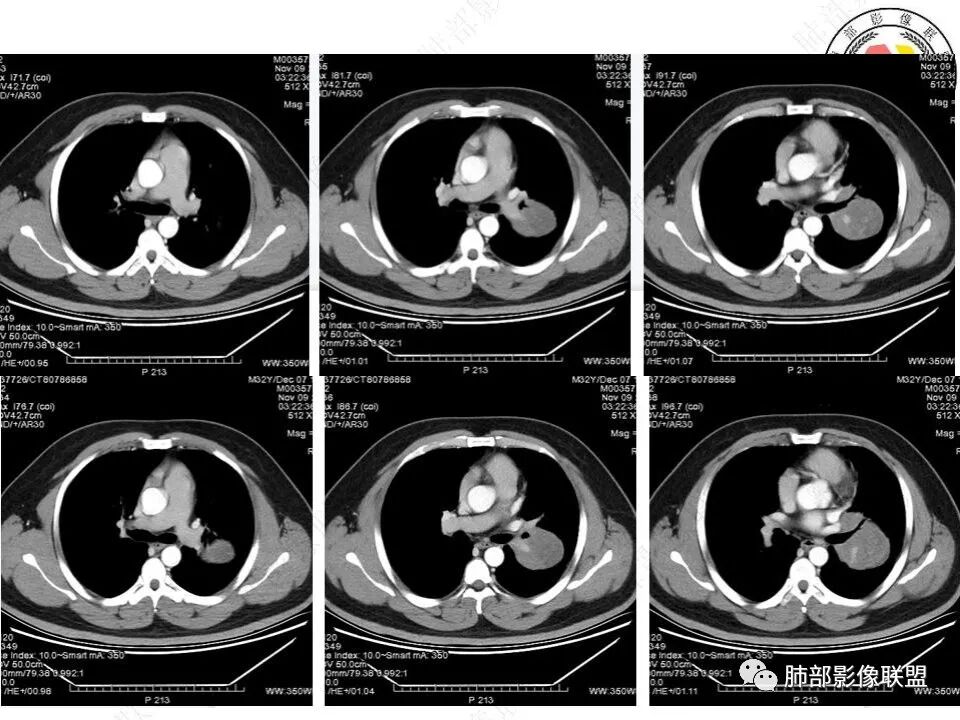

青年男性患者,体检发现左肺下叶类圆形占位性病变,骑跨叶间裂,左肺下叶支气管受压内移,边界清楚,浅分叶,内部密度不均匀,动脉期见分支状血管,渐进性强化,远端见空气新月征?坏死?定位胸膜,考虑恶性sft,癌肉瘤待排

青年男性,体检发现左肺不规则类圆形占位性病变,叶间裂区域,定位胸膜来源。左肺下叶支气管受压狭窄,但管壁光整,未见腔内阻塞或管壁受侵。包块边界清晰,浅分叶,内部密度不均匀,病灶后份见空气新月征。渐进性强化,增强动脉期见分支状血管,蛇纹血管征。肺门纵膈未见增大淋巴结,符合孤立性纤维瘤(SFT)。

1)形态、大小:一般为单发,较小者呈类圆形或椭圆形,较大者呈浅分叶或不规则状;大小差异较大,直径1-25cm(有2个高峰期,大多数肿瘤直径<5cm,或者>10cm),肿瘤的大小与发生部位、病程长短有关;

3)肺部SFT好发于肺表面如叶间裂等区域,定位相当重要。肿块边界清楚光整,支气管不受侵(或可受压推移)。CT平扫肿瘤多呈等或稍低密度。发生于脑膜的SFT平扫肿瘤多为略高密度病,类似脑膜瘤;肿瘤较小者密度均匀,较大者内部密度常不均匀、见多发灶性或不规则形中心低密度区(细胞稀疏区含有丰富胶原纤维易发生黏液样变性或囊性变),钙化少见。

5)肿瘤的强化程度及方式:增强扫描肿瘤早期实性成分呈不均匀斑片或斑驳样强化,亦可呈“ 地图样” 明显强化,强化程度不一,可呈轻度-显著强化;静脉期持续强化,多期增强及动态增强扫描均呈“快进慢出”型强化,且强化范围逐渐增大并趋均匀。肿瘤内部及周围常见多发粗细不等强化或流空肿瘤血管影。瘤体内“蛇纹血管”在其他诸如硬化性肺细胞瘤、错构瘤等等是非常罕见的。